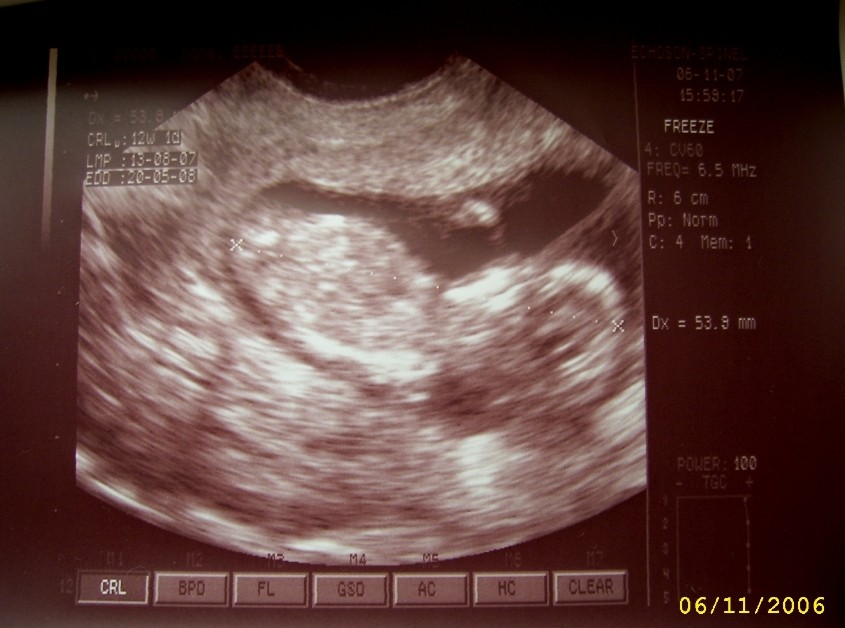

Właśnie wróciłam od lekarza, jest wszystko OK. Dzidzia zdrowa, oglądałam ją z każdej strony, spała z nogami po turecku

nawet rączkę miała troszkę w górze, mały akrobata rośnie.

Według USG to 12 tydzień i 1 dzień.

Lekarz zrobił przeziernośc karku i też jest wszystko OK. Jednak dzidzię podsłucham dopiero później, może za miesiąc, mówił że na wszystko będzie czas, troszkę chyba się śpieszył.